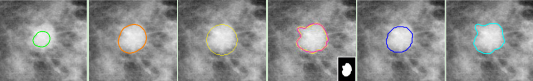

袁景团队在Pattern Recognition发表研究成果